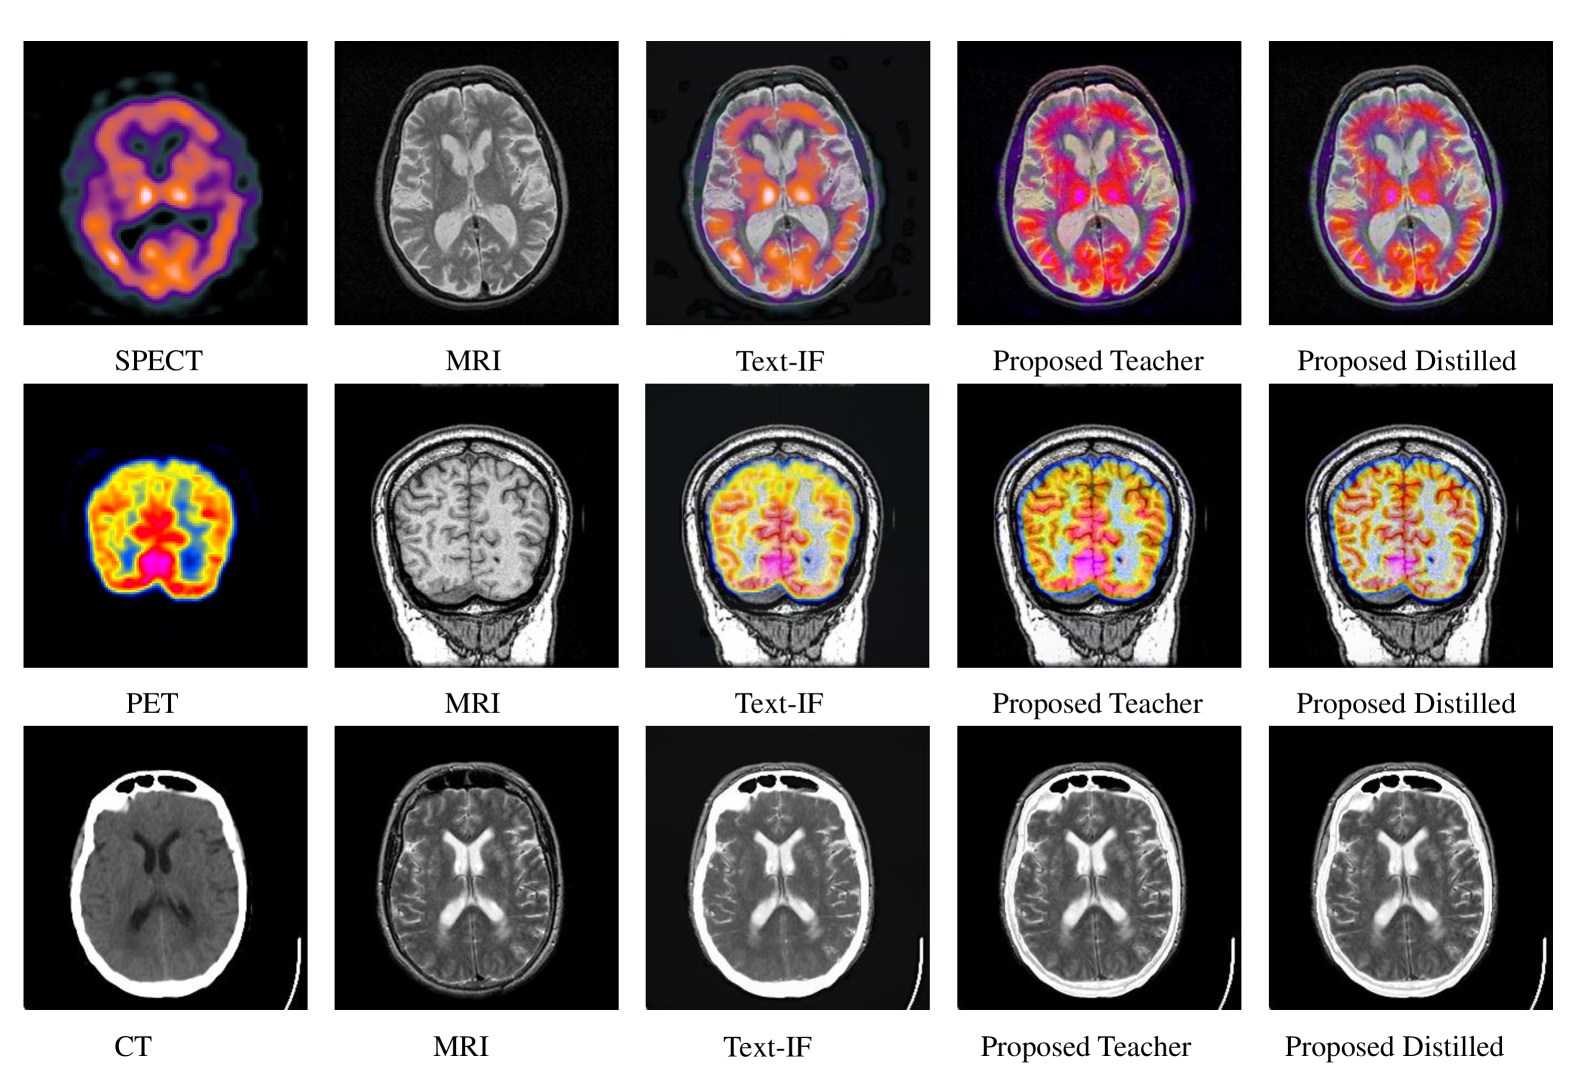

Refer to caption

Figure 4: Compare with previous SOTA text-guided image fusion method Text-IF on Havard Medical Image Fusion Datasets. More can be found in appendix.

For SPECT-MRI fusion, our method shows notable advantages in preserving functional information while maintaining anatomical details. In CT-MRI fusion, where structural alignment is critical, our approach achieves the highest SSIM scores, indicating better structural preservation. The PET-MRI results further confirm our method’s effectiveness in handling multi-modal medical images with different characteristics. Figure4 presents visual examples from different medical modalities. Our fusion results exhibit better detail preservation and contrast enhancement, which is essential for clinical applications. The distilled student network maintains these advantages while significantly reducing computational requirements, making it more practical for clinical deployment.

C.2 Visual Comparison on Medical Images

Figure 9 showcases detailed visual comparisons across different medical imaging modalities. The results highlight our method’s advantages in: 1) Preserving fine anatomical structures from both modalities 2) Maintaining clear tissue boundaries and contrast 3) Effectively combining functional information (PET/SPECT) with anatomical details (MRI) 4) Producing clinically meaningful fusion results with enhanced diagnostic value